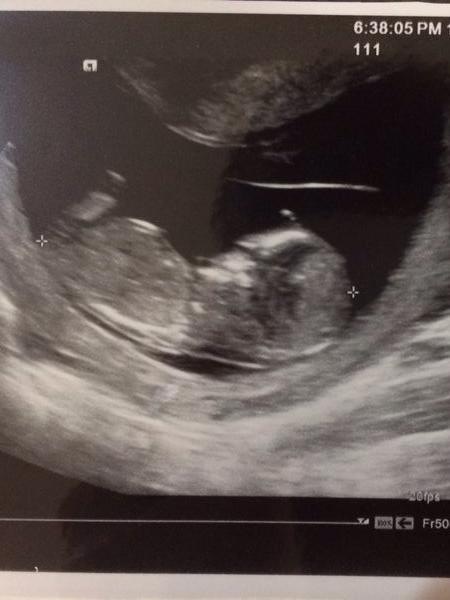

。二寶。禾馨婦產科高層次超音波~原來你長這樣子!!

懷小蜜蜂時~總覺得在振興的孫大威醫生每次都很仔細的照超音波

所以,原本想說這一胎也就不用多花錢去照"高層次超音波"

只是~也許近年來真的有太多太多的醫療糾紛~

連醫生自己也會鼓勵產婦也去照個"安心"

畢竟多2個人幫自己再確認小朋友的健全~